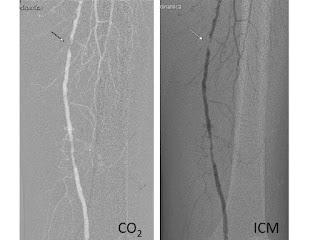

кръвоностната система поведението на CO2 е напълно различно от това на йодният

контраст. Липсата на вискозитет позволява значително по-добро контрастиране на

колатералната мрежа и на изолирани проходими участъци на артериалната система. Характерно за ангиографските изображения с СО2 е че са

визуализират като негативни, за разлика от тези при инжектиране на йод базиран

контраст.